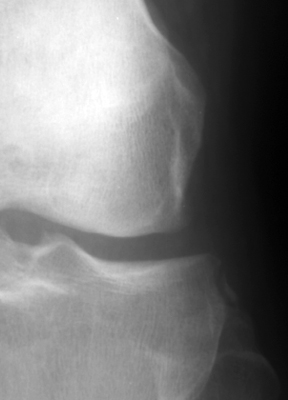

Diagnosis:ACL Tear - Segund fracture Discussion:Frontal radiographs of the knee which reveal a small fleck of bone adjacent to the lateral aspect of the lateral tibial plateau. This "lateral capsular sign" is a simple radiographic finding visible on the routine AP knee x-ray, which indicates severe lateral capsular injury and should alert the examiner to the possibility of ACL tear. The fleck of bone represents an avulsion of the meniscotibial portion of the middle one-third of the lateral capsular ligament. It most commonly implies a disruption of the capsular ligament and the ACL. A-B Radiographs. C. MRI confirms the diagnosis of ACL tear. References: